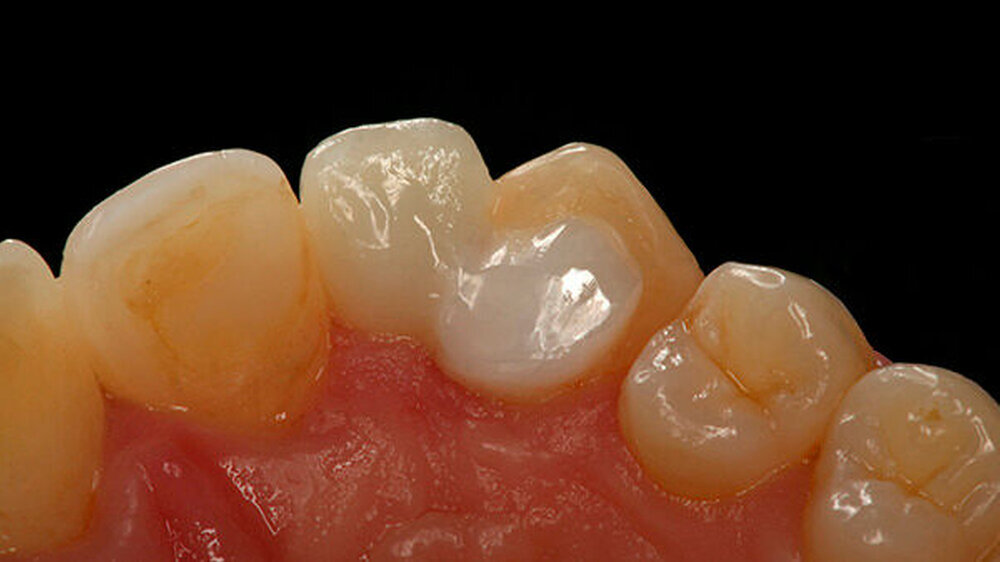

Beispiele für individuellen ZE

Die Jahrestagung der Deutschen Gesellschaft für Prothetische Zahnmedizin und Biomaterialien (PGPro) in Ulm geht der Frage nach, welche Versorgungskonzepte - mit guten Langzeitergebnissen - individuell und preiswert machbar sind. Gute Beispiele finden Sie in unserer Bilderstrecke!